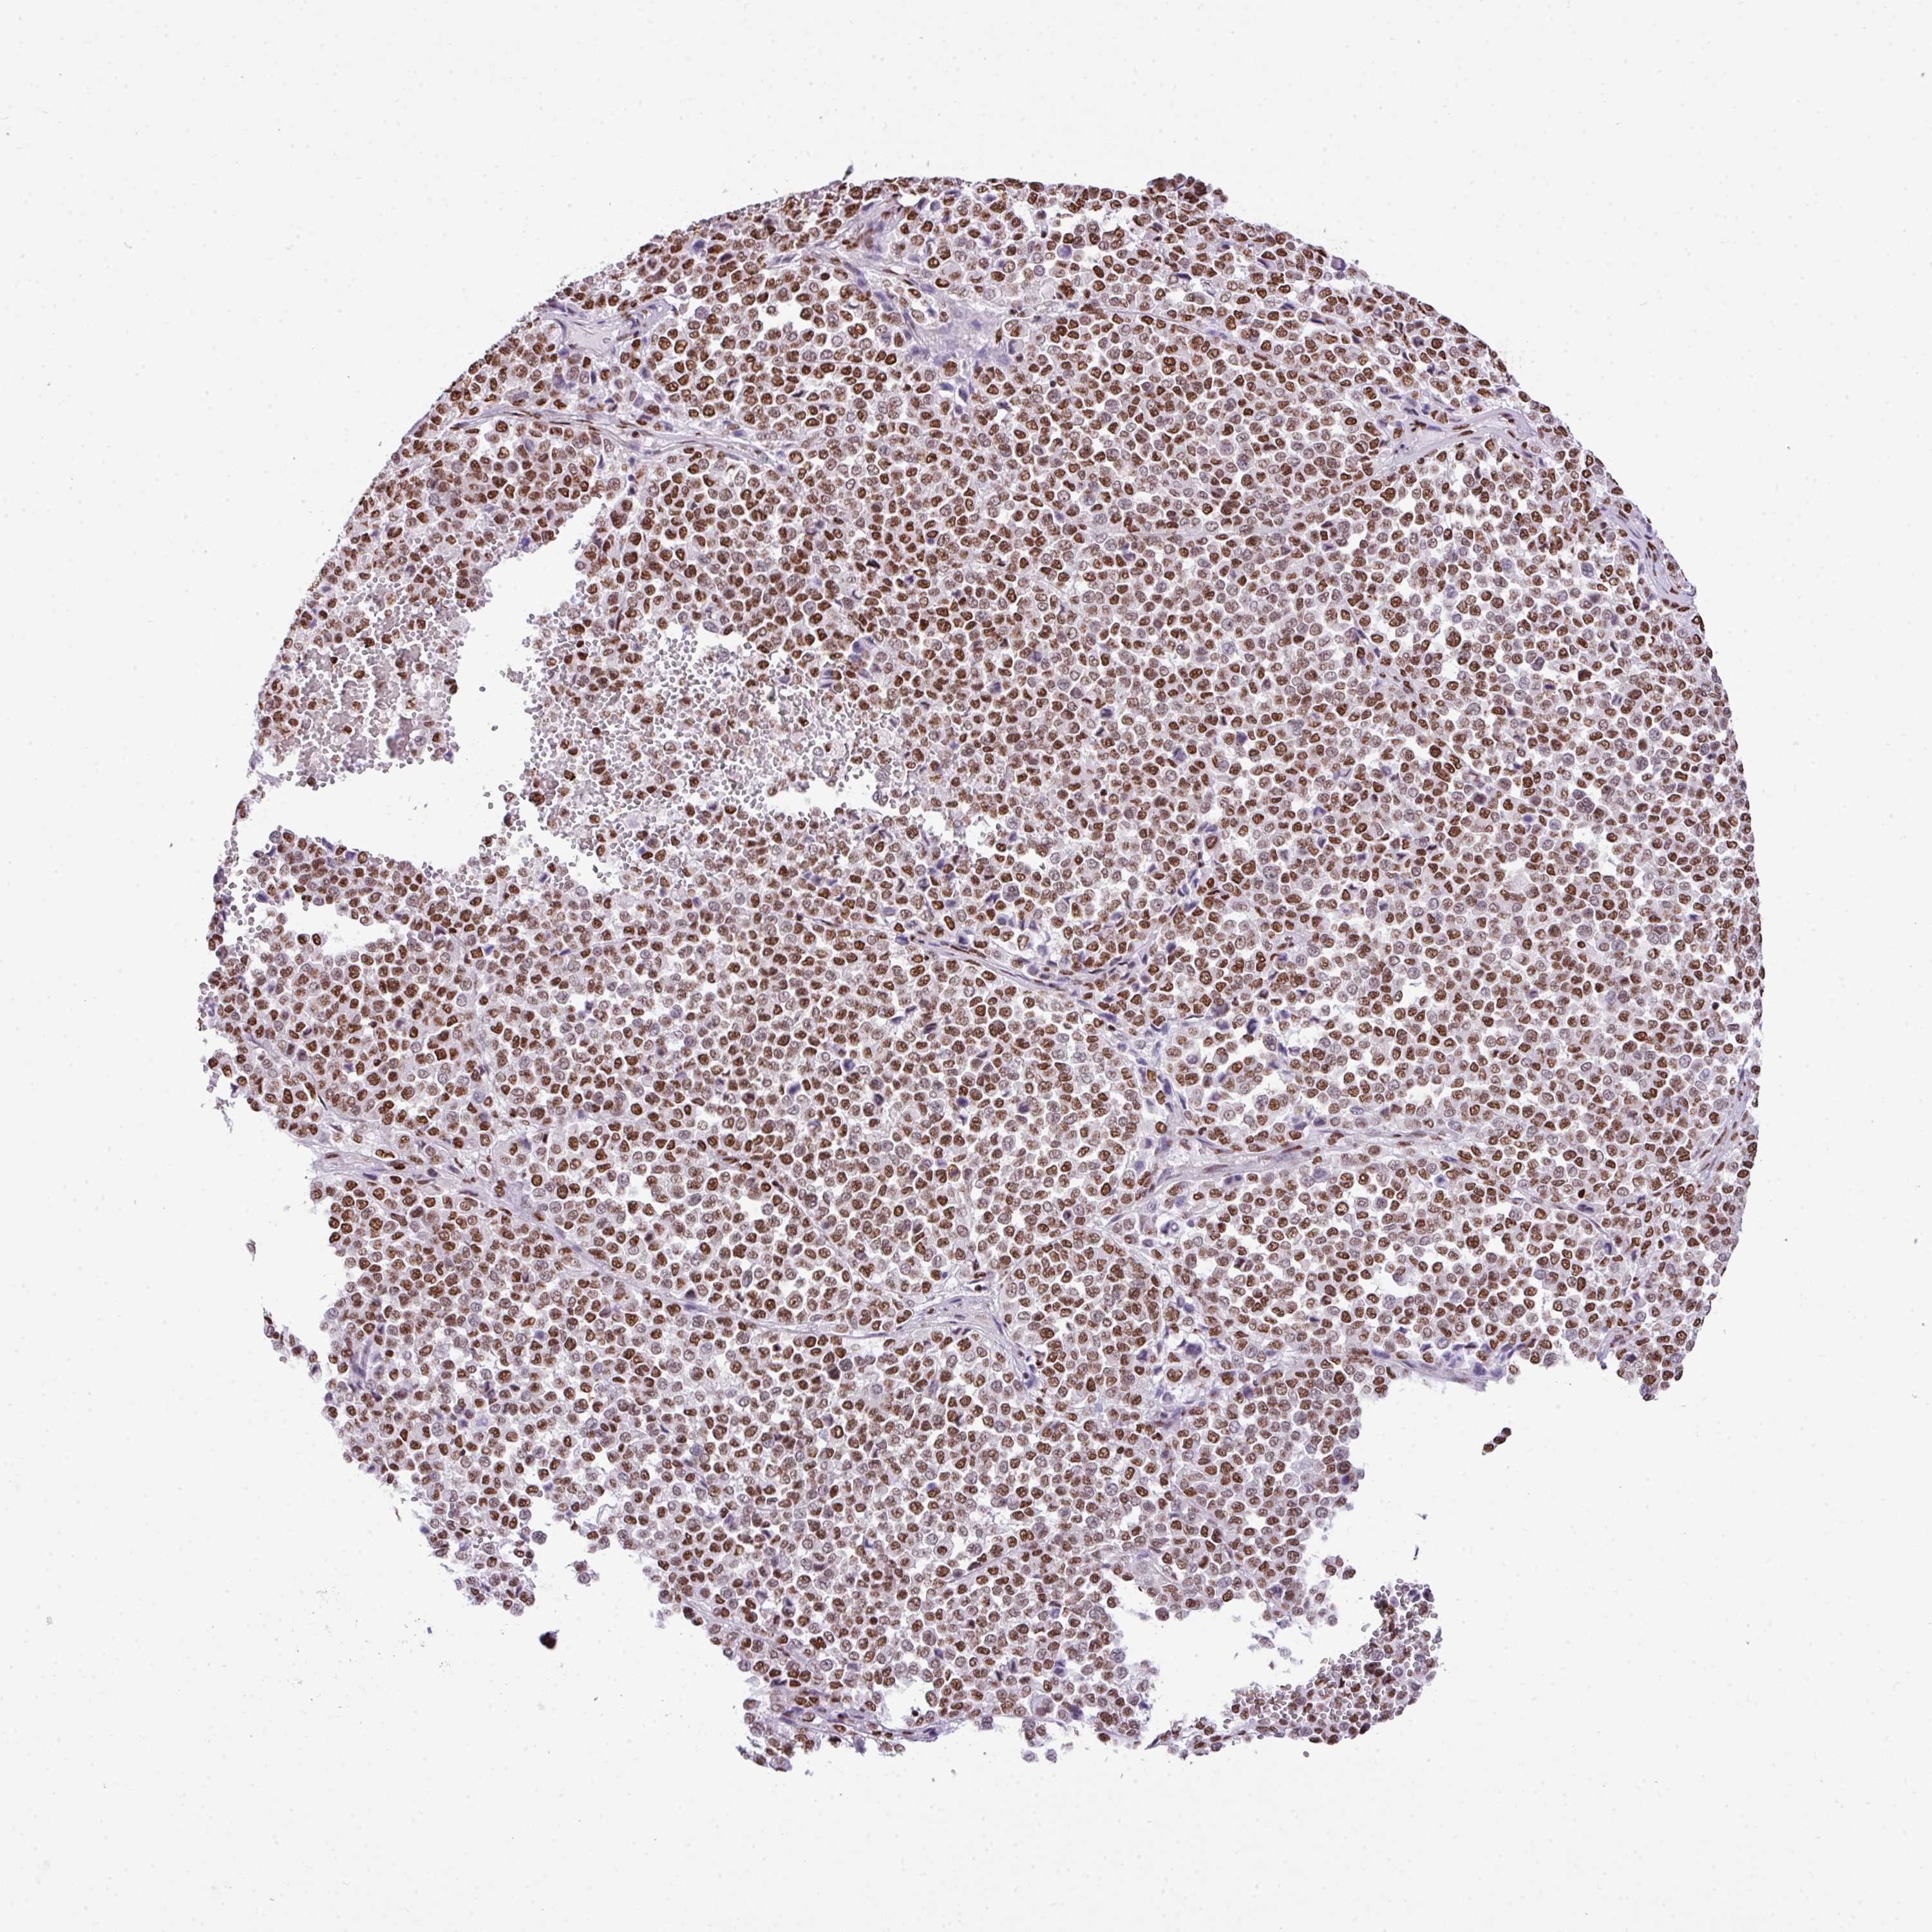

MELANOMA - Protein expressioni

A mouse-over function shows sample information and annotation data. Click on an image to view it in a full screen mode. Samples can be filtered based on level of antibody staining by selecting one or several of the following categories: high, medium, low and not detected. The assay and annotation is described here.

Note that samples used for immunohistochemistry by the Human Protein Atlas do not correspond to samples in the TCGA dataset.

Antibody stainingi

Antibody staining in the annotated cell types in the current human tissue is reported as not detected, low, medium, or high, based on conventional immunohistochemistry profiling in selected tissues. This score is based on the combination of the staining intensity and fraction of stained cells.

Each image is clickable and will lead to virtual microscopy that enables deeper exploration of all samples and also displays staining intensity scores, fraction scores and subcellular localization as well as patient and tissue information for each sample.

Antibody HPA053883

Staining

High

Medium

Low

Not detected

Intensity

Strong

Moderate

Weak

Negative

Quantity

>75%

75%-25%

<25%

None

Location

Nuclear

Cytoplasmic/membranous

Cytoplasmic/membranous,nuclear

Malignant melanoma, NOS